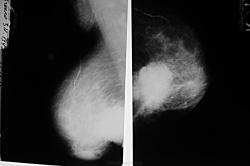

Да, в грудной полости, весьма скоро будет "фарш".

А, возможно, и не только в грудной полости.

Тут помимо основного узла или даже лучше сказать узлов имеются вторичные инфильтративно-отечные изменения молочной железы с переходом в аксиллярную область. Любопытно, а нет ли в ребрах изменений Печальный случай...

Что-то мне кажется, что в среднем грудном отделе позвоночника "кашица". А боковой рентгенограммы нет?

Иллюстрации ОГК.